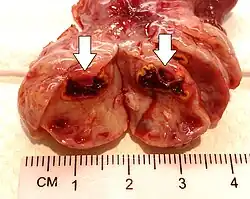

Corpus luteum cyst